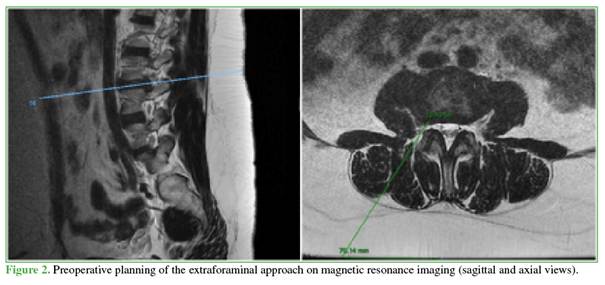

Under general anesthesia, the patient is placed in the prone position. Unlike the transforaminal technique, a posterolateral approach is used and planned based on preoperative imaging (Figure 2), as extraforaminal disc herniations do not require a highly lateral entry point. This technique is technically challenging at the L5 S1 level due to interference from the iliac crests, making it more suitable for levels L4 L5 and above.

A strict anteroposterior fluoroscopic view is obtained to visualize endplates parallel to the target disc. The midline is marked, followed by lateral marking according to the preoperative plan. The dilator is inserted and the endoscope is advanced. Fluoroscopic confirmation of correct positioning is performed. When planning is accurate, the extraforaminal disc herniation is usually the first structure visualized (Figure 3).